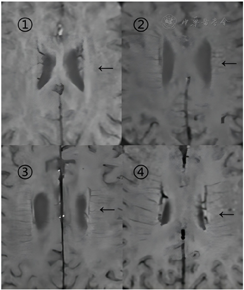

选取患者SWI序列上基底神经节到侧脑室消失为止的连续数个层面进行评分,采用Adobe Photoshop 2021软件进行高反差保留等处理,从而进一步提高图像清晰度。对每一层面进行脑叶分区,分为左侧额叶、左侧顶叶、左侧枕叶、右侧额叶、右侧顶叶、右侧枕叶六个区,根据DMVs不同的可见性与突出性对每个区域分别进行评分,评分为0~3分(图1)。得到各脑叶分数并进行求和得到DMVs总分[8]。

注:①中箭头所示为深髓静脉征(DMVs)不可见,DMVs总分0分;②中箭头所示为DMVs轻微可见,DMVs总分1分;③中箭头所示为DMVs中度可见,DMVs总分2分;④中箭头所示DMVs显著可见,DMVs总分3分